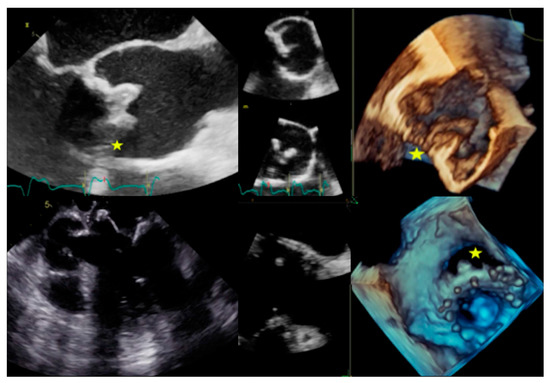

6.2. When to Ask for TTE and When to Ask for TOE

| Left-sided IE | Good visualization of mitral and aortic valve. Valvular dysfuction assessment. Identification of complication (i.e., valvular regurgitation). | Difficult differential diagnosis in presence of marantic vegetations or high calcification. | Detection of vegetations and valve perforation. Assessment of perivalvular extent of disease (abscesses, pseudoaneursysm, fistula). | Inferior to TTE/TOE in detecting small vegetations (<2 mm). | Prognostic assessment: simultaneous detection of embolism, metastatic lesions and portal of entry. | Limited sensitivity for small vegetations. | Evaluation of distant emboli and portal of entry. | Limited role because of low sensitivity for small vegetations. | Capability to assess vegetations (inferior to TTE/TOE). Capability to assess local complications. Independent by acoustic window. May detect concomitant myocardial inflammation. | Not included in current guidelines for IE diagnosis. |

| PVE | Routinely used for follow up; it allows sequential assessment of prosthesis function. TOE is often required to correctly assess the prosthesis. | Limited by prosthetic material artifacts (i.e., acoustic shadow). Early complication (i.e., abscess) can be difficult to identify. | Identification of complications (paravalvular leakage, abscesses, pseudoaneurysm, dehiscence, and extension to adjacent structures). Capability to visualize large vegetations (>10 mm). | Low image quality for beam hardening artifacts. Limited in assessing small vegetations (<4 mm). | High diagnostic accuracy. Good assessment of perivalvular/periprosthetic complications. Reduction of rate of misdiagnosed PVE. Role in prediction of MACEs. Prognostic significance. | Host reaction may reduce specificity (risk of false-positive studies until 3 months after surgery). | High specificity for infection. Reduction of rate of misdiagnosed PVE. Differential diagnosis between septic and sterile vegetations. | Limited sensitivity for small lesions. | Image quality severely hampered by susceptibility artifacts (especially from mechanical prostheses). | |